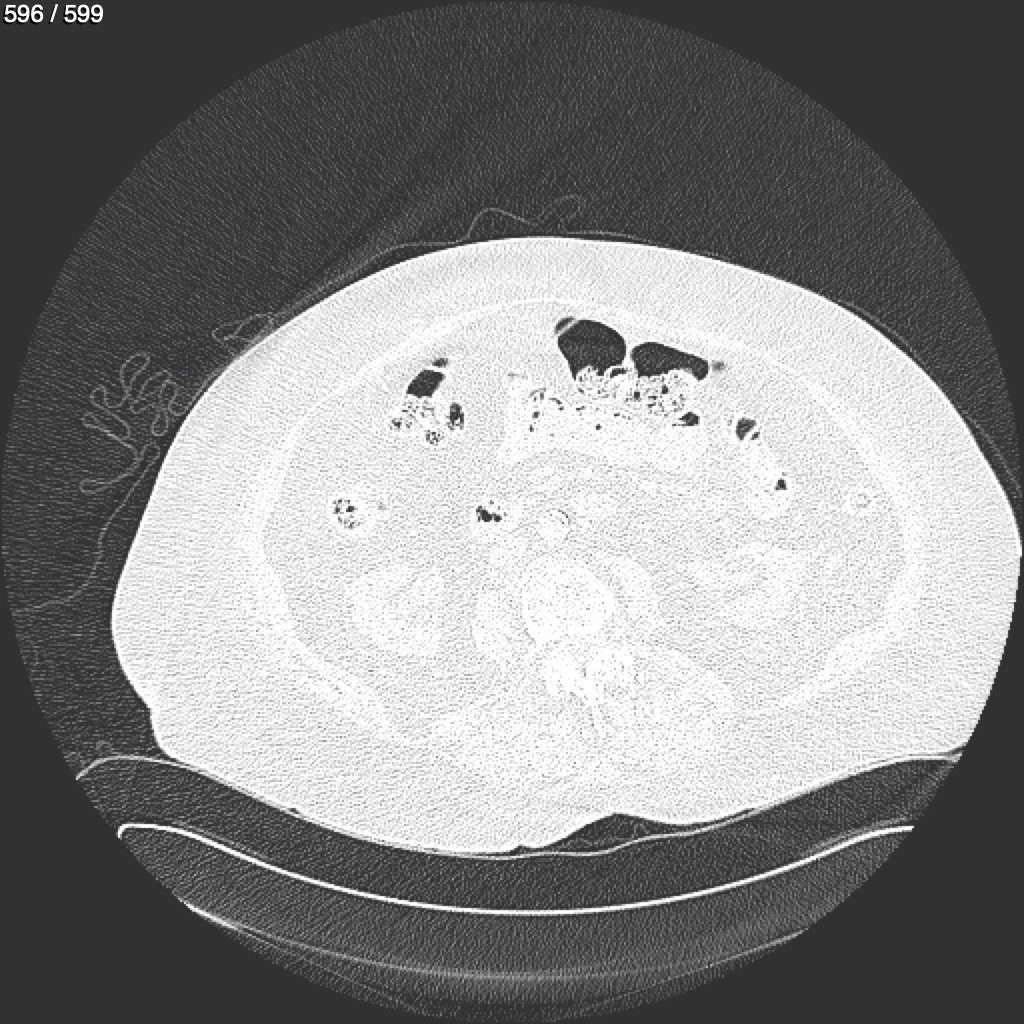

Home G​l​o​r​i​a​ ​G​l​a​d​y​s​ ​B​e​a​s​l​e​y​ ​-​ ​T​ó​r​a​x​ ​T​o​r​a​x​_​S​i​m​p​l​e​ ​(​A​d​u​l​t​o​)